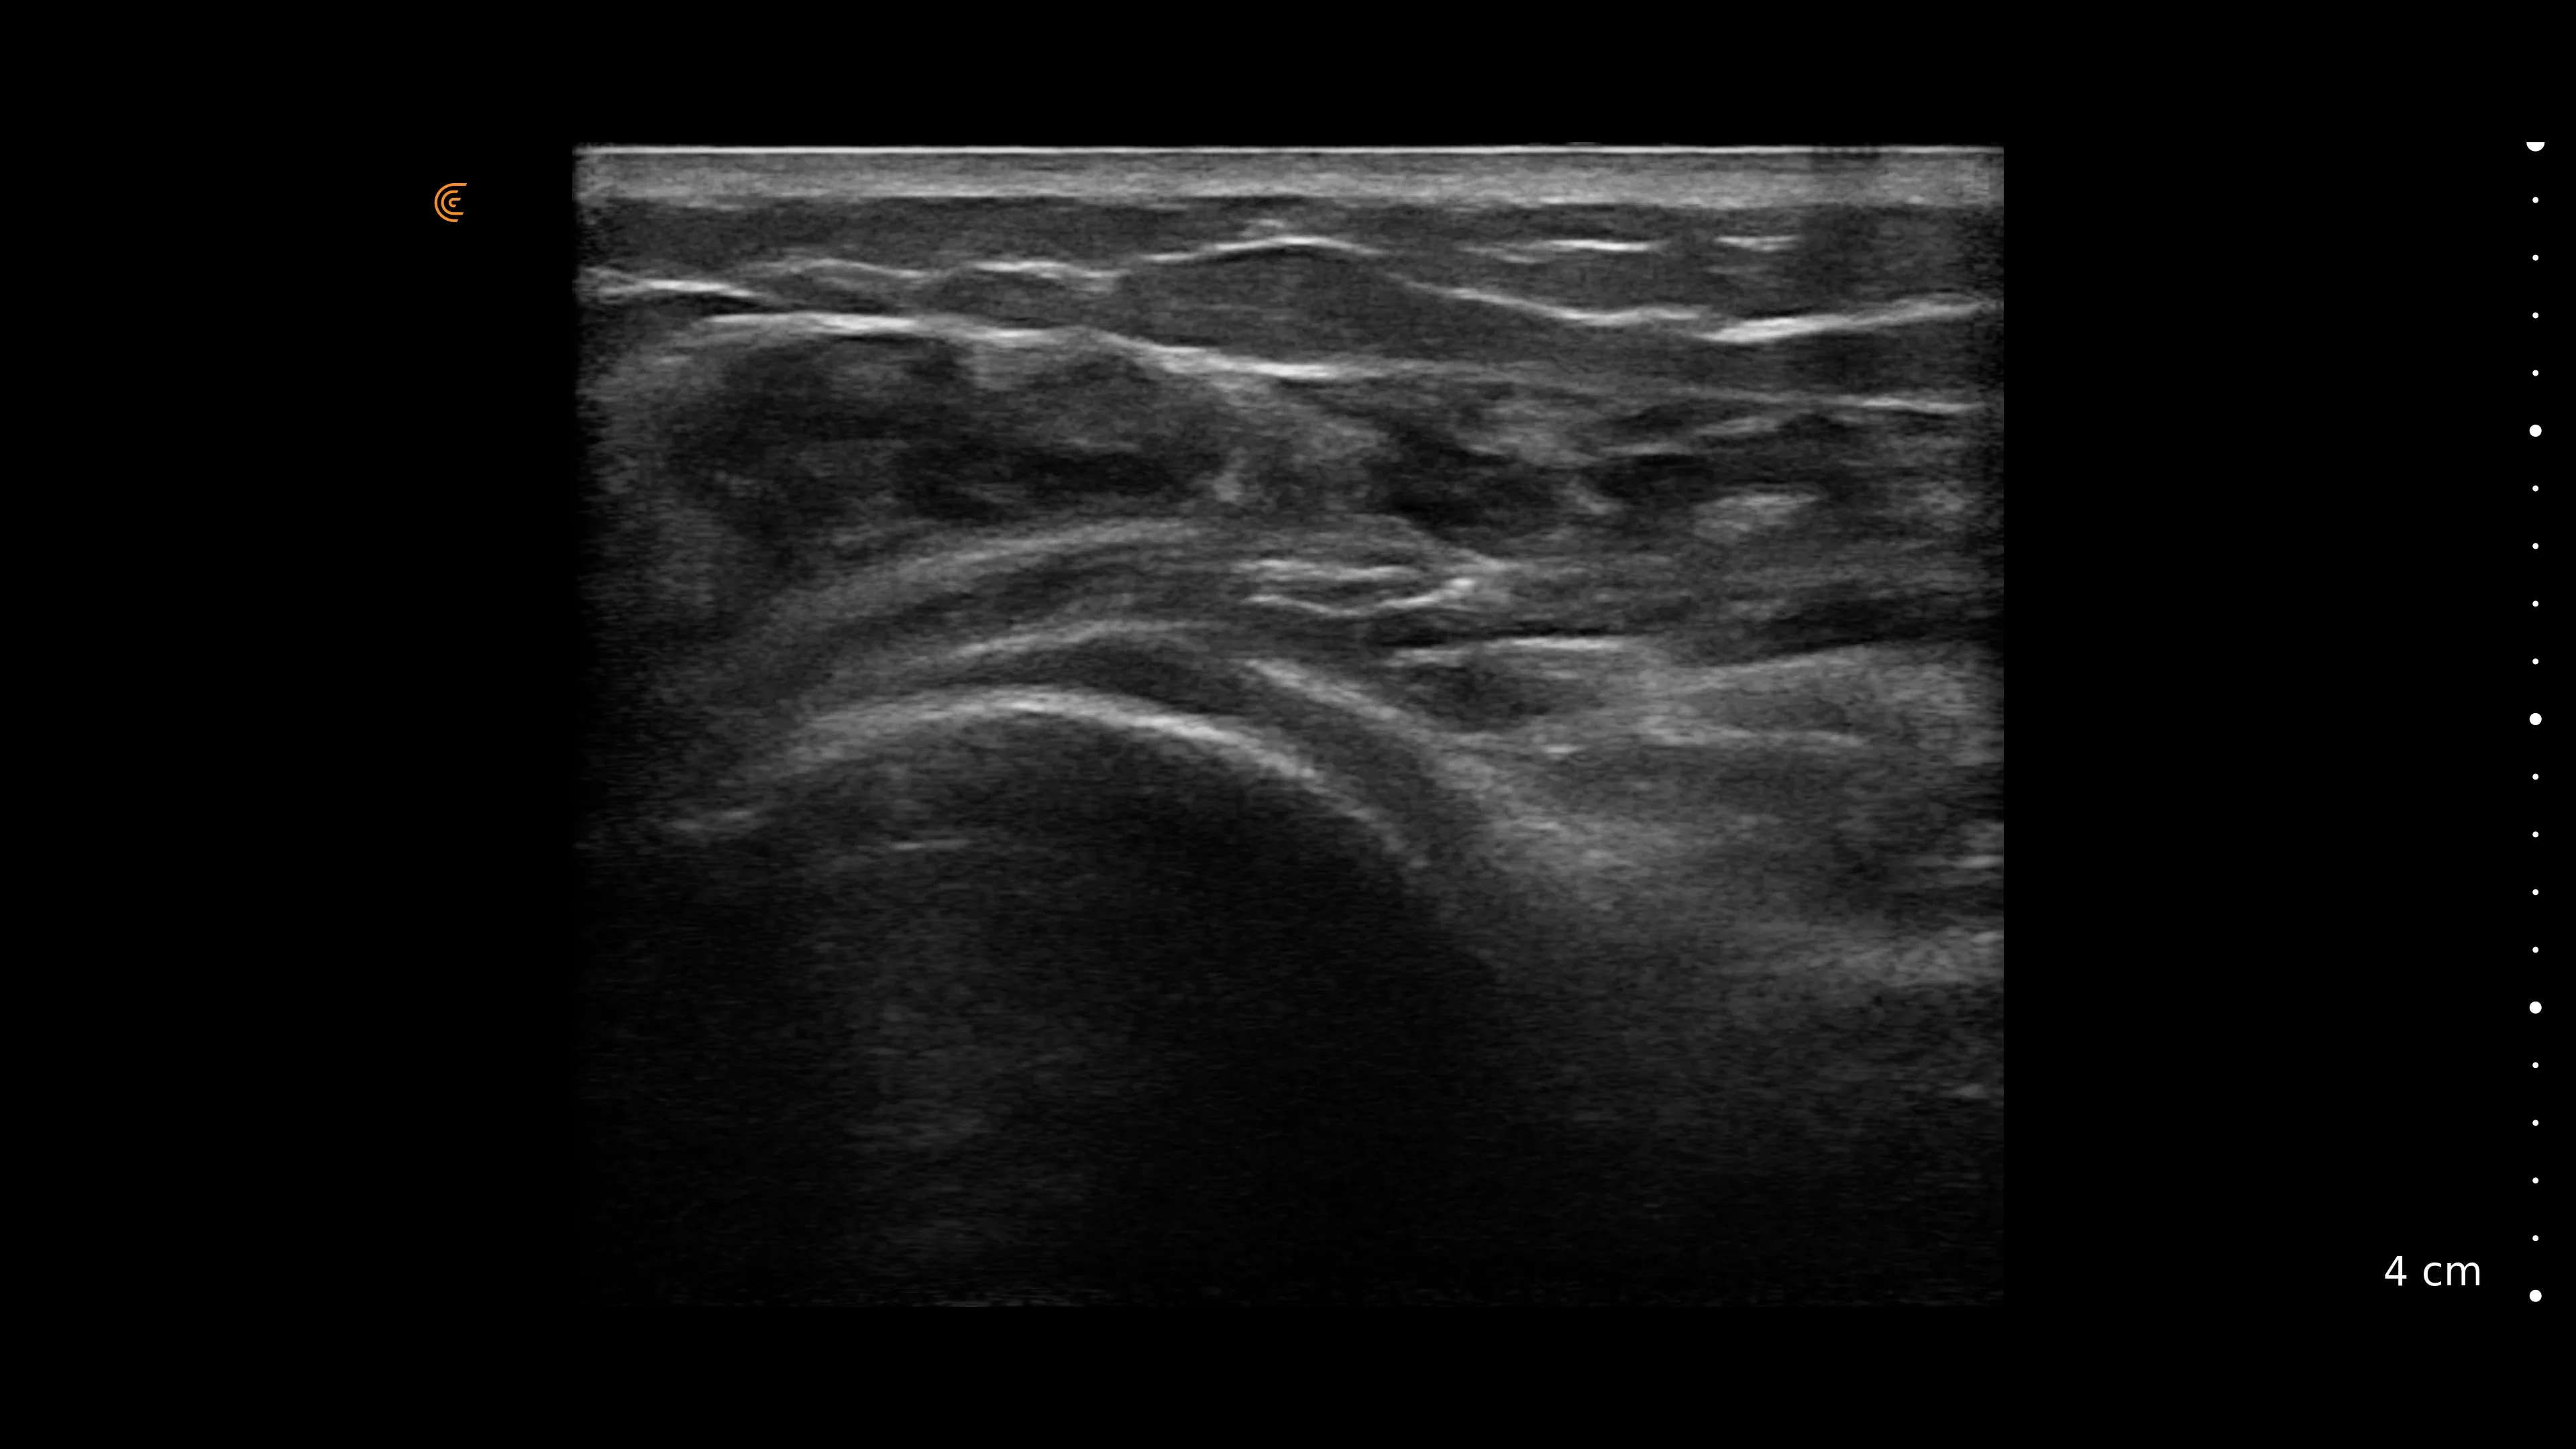

Ultrasoundguided intraarticular injection of the shoulder joint

Ultrasoundguided intraarticular injection of the shoulder joint Frozen Shoulder Ultrasound Guided Injection ultrasound (usg) guidance allows visualization of the shoulder anatomy and improves the accuracy of the injection site. blind versus guided glenohumeral joint injection. multiple versus single ultrasound guided suprascapular nerve block in treatment of frozen shoulder in diabetic. adhesive capsulitis (ac), also referred to as ‘frozen shoulder’ and ‘pericapsulitis’, is characterised by progressively worsening. A guided. Frozen Shoulder Ultrasound Guided Injection.